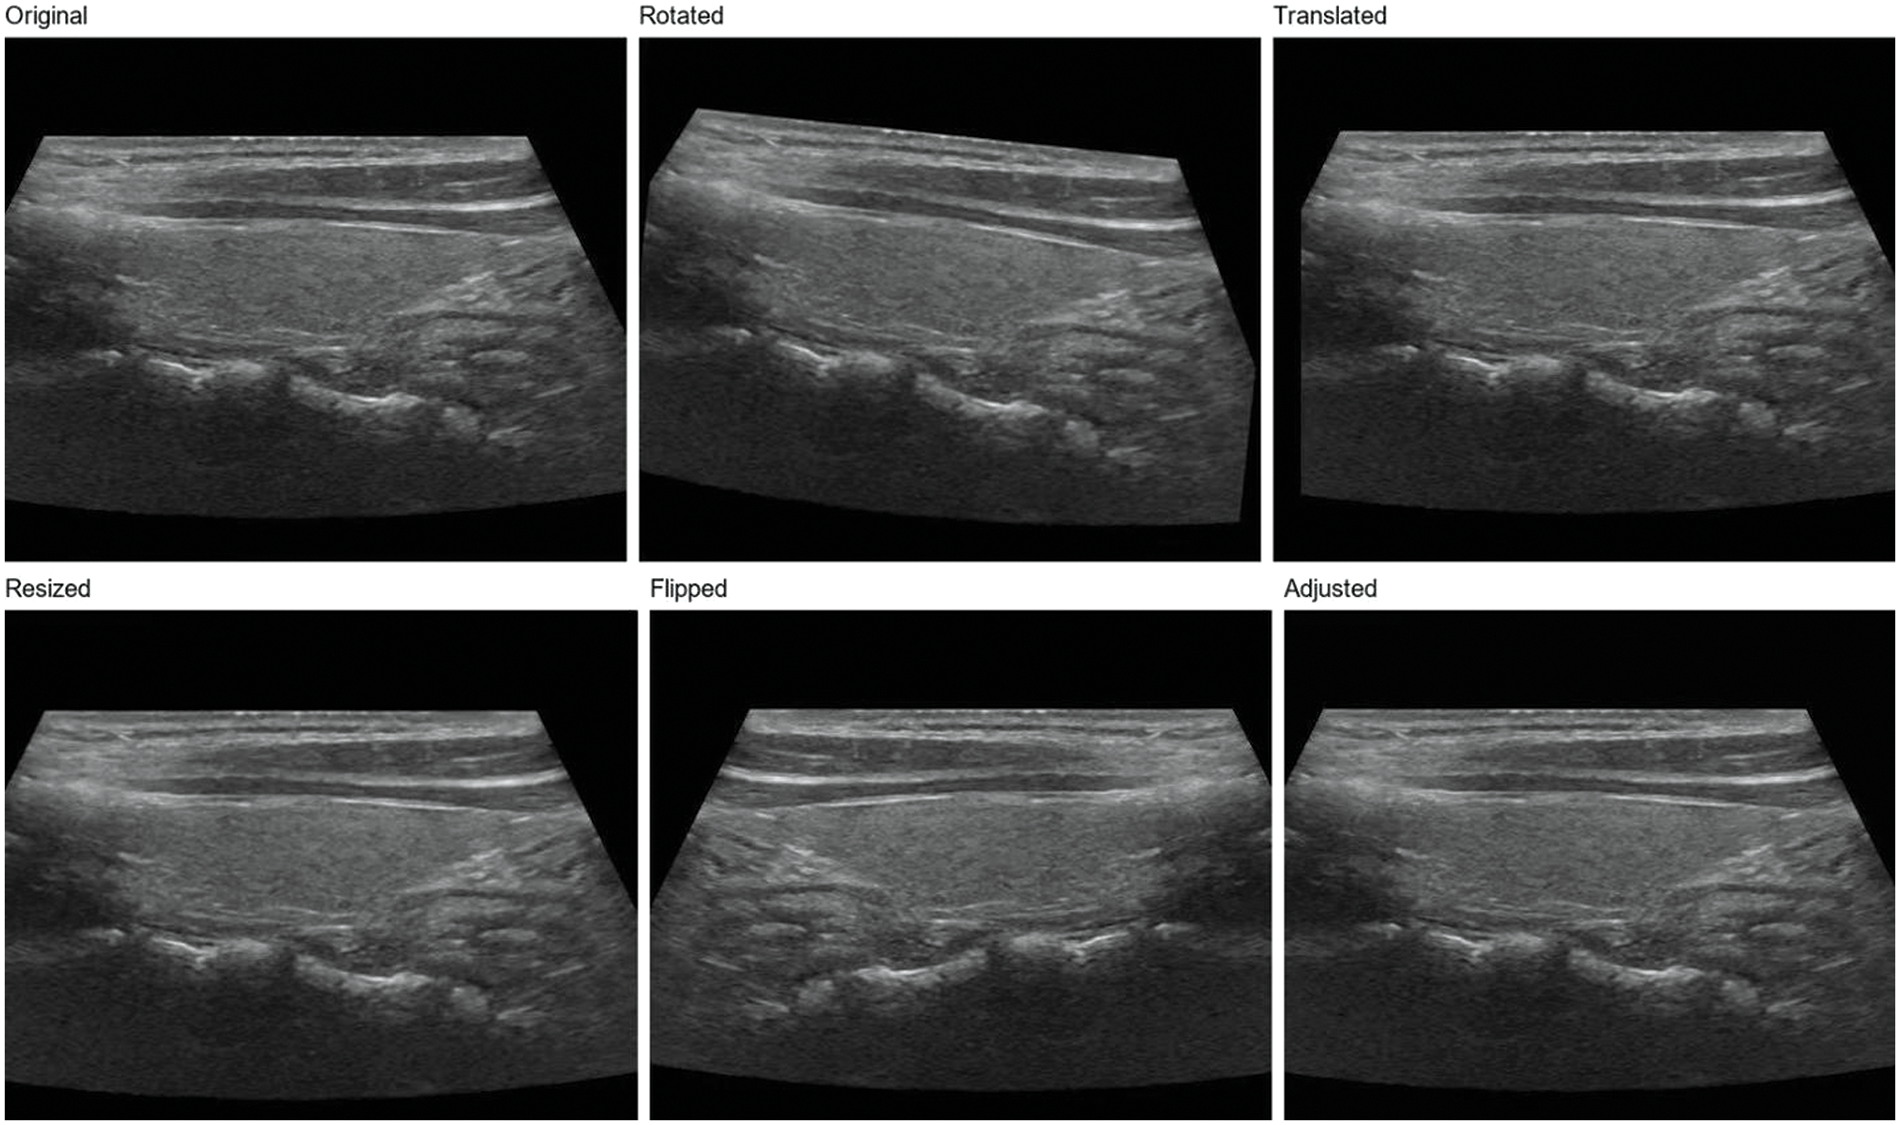

In order to further enhance the model’s generalization ability, we adopt a data augmentation strategy [11]. Data augmentation generates new training samples through various image transformations, thus enlarging the scale of the training set. In this study, we used the following data augmentation methods:

Rotation: The image is rotated at random angles, ranging from −15 to 15 degrees. This helps the model adapt to nodular images from different angles.

Translation: The image is translated horizontally and vertically at random with a range of 5% of the image width and height. This helps the model adapt to different positions of the nodules in the image.

Zoom: The image is randomly scaled with a range of 0.9 to 1.1 times. This helps the model adapt to nodules of different sizes.

Flip: The image is flipped horizontally. This helps the model adapt to nodules in diverse directions [40].

Contrast and brightness adjustment: The image is randomly adjusted for contrast and brightness, varying from 0.8 to 1.2 times. This helps the model adapt to images with different contrast and brightness [41].

Using these data enhancement methods, as shown in Fig. 2, we can significantly improve the model’s generalization ability and enhance its performance when handling actual clinical data. Simultaneously, data augmentation also is used to reduce overfitting and improve model performance on validation and test sets [42]. In the subsequent experiments, we will evaluate the effects of numerous data augmentation methods on ThyroidNet’s performance to select the best augmentation strategy.

Figure 2: Thyroid nodule image enhancement